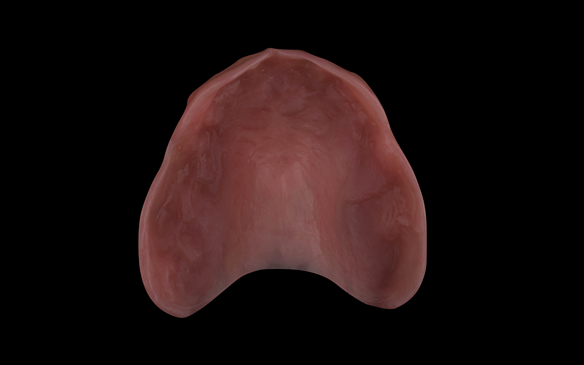

- Definitive dentures (Mk 2) – complete upper metal reinforced and lower cobalt chromium based partial of hygienic Scandinavian design to be made 9 - 12 months after extractions of all upper teeth and LR5 and LL4

The clinical situation and treatment process is shown in detail below with photographs.

The patient has been successfully rehabilitated and is now having periodontal maintenance from Syed Abad, Specialist in Periodontics at the practice. His quality of life has improved considerably. The clinical prosthodontics was provided by me and the technical work by Rowan.